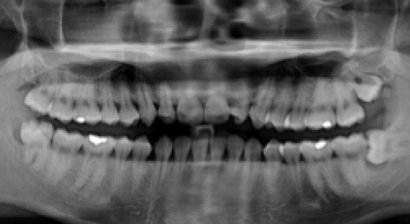

Der Weisheitszahn Der Weisheitszahn ist von der Mitte aus gezählt der achte Zahn im menschlichen Gebiss. Normalerweise hat ein Mensch vier Weisheitszähne, in jedem Gebissquadranten einen. Sie brechen meist erst im Erwachsenenalter, teilweise gar nicht durch. Die Anzahl der Wurzeln ist unte...